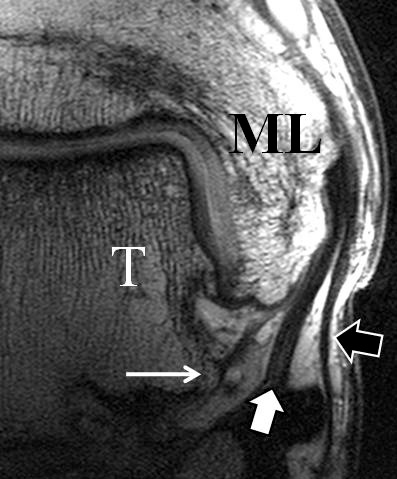

Man unterscheidet bei dem Ligamentum deltoideum eine tiefe Schicht (Pars tibiotalare posterior, Pars tibiotalare anterius) und eine oberflächliche Schicht (Pars tibionaviculare, Pars tibiocalcaneare, Pars tibiotalare posterius superficialis und Tibiospring-Ligament) 10. Hochauflösende Techniken lassen eine differenzierte Beurteilung aller Bandanteile zu. Sowohl rein ligamentäre als auch osteo-ligamentäre Ausrisse sind normalerweise gut zu erkennen. Die Pars tibiotalaris posterior ist multifaszikulär aufgebaut und sowohl axial als auch coronar (Abb. 19 a) gut bildgebend abzugrenzen. Die deutlich kleinere, nur inkonstant angelegte Pars tibiotalare anterior inseriert an einem kleinen Talustuberkel (Abb. 19 b). Ossäre Bandausrisse kommen hier gehäuft vor. Proximal verlaufen die Pars tibiocalcaneare und die Pars tibionaviculare gemeinsam (Abb. 19 c) nach kaudal und trennen sich dann in zum Calcaneus und zum Os naviculare ziehende Bündel auf. Ein besonderer Typ ligamentärer Verbindungen stellt das Tibiospring-Ligament dar. Es verbindet nicht wie für Ligamente typisch zwei Knochen miteinander, sondern es hat seinen ossären Ursprung an der Tibia und inseriert am Pfannenband (Ligamentum calcaneonaviculare plantare, im englischen Schrifttum Spring-Ligament genannt), also nicht ossär. Das Innenband ist mit 60% der Verletzungen am häufigsten betroffen. Isolierte Innenbandverletzungen sind jedoch selten. Sie treten gehäuft assoziiert mit Syndesmosenläsionen, Fibulafrakturen, Verletzungen des Muskulus tibialis posterior und des Pfannenbandes auf (H.-K. Beyer 2003). Entsprechend sollte auf diese Kollateralverletzungen bei der Beurteilung geachtet werden. Eine weitere Folge von Verletzungen des Ligamentum deltoideum ist die chronische Sprunggelenksinstabilität. Arthroskopisch weisen hier bis zu 40% der Patienten einen elongierten Verlauf des Ligamentum deltoideum auf. In diesem Patientenkollektiv besteht auch eine erhöhte chondrale Komorbidität mit arthroskopisch erkennbaren Knorpelschäden (98%) im Gegensatz zu der Patientengruppe (66% Knorpelschäden) mit reiner Außenbandinstabilität 11. Dies belegt die klinische Bedeutung von Innenbandverletzungen.